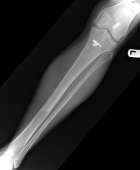

C.G. – 21 year old white female college lacrosse player with four month history of left shin pain worsened by activity. Physical exam demonstrates TTP overlying distal left tibia, extremity NVI.

Zoom image: Radiological image Radiological image.